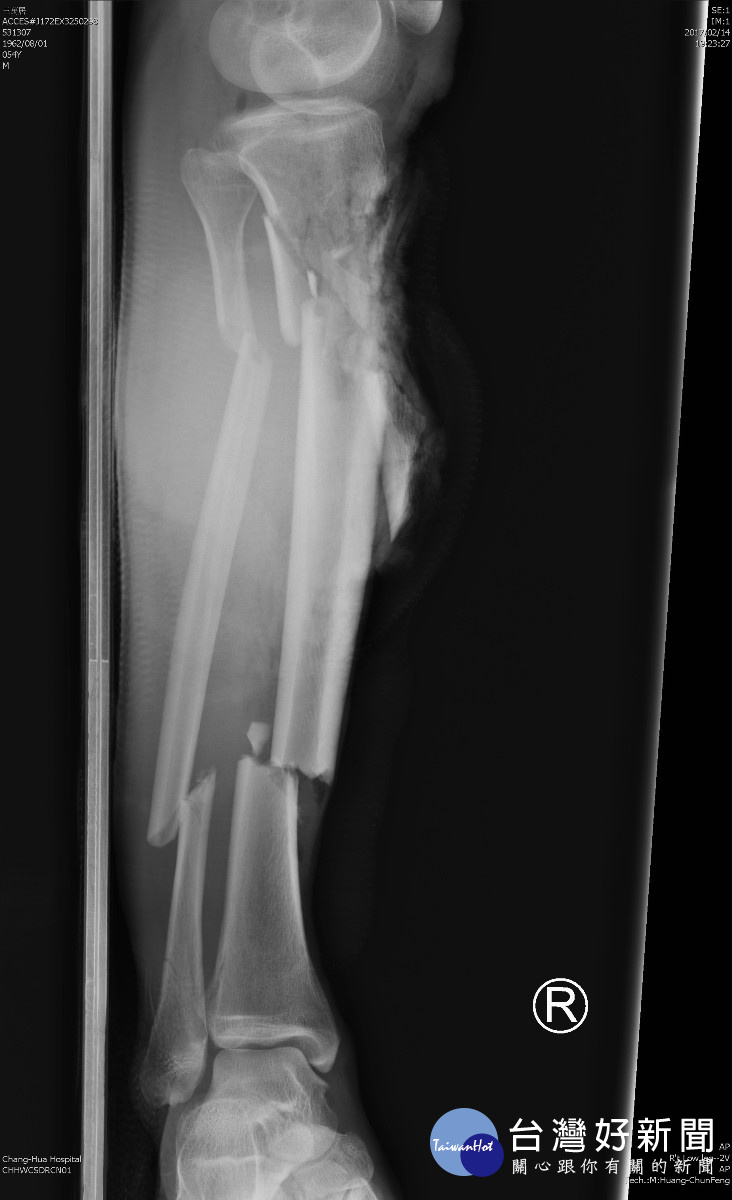

醫師呂明川指出,王先生在3個月前被機車高速撞傷,當天到達急診室時右小腿嚴重開放性骨折,並且大量失血,經X光顯示,脛骨、腓骨共6大處碎裂,小碎裂不計其數,還合併膝蓋下、脛骨外大面積的軟組織缺損,也就是皮肉都不見了,使得脛骨外露,情況慘不忍睹,已達開放性骨折古氏分類的第三級,情況相當危急。